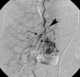

Internal mammary varices